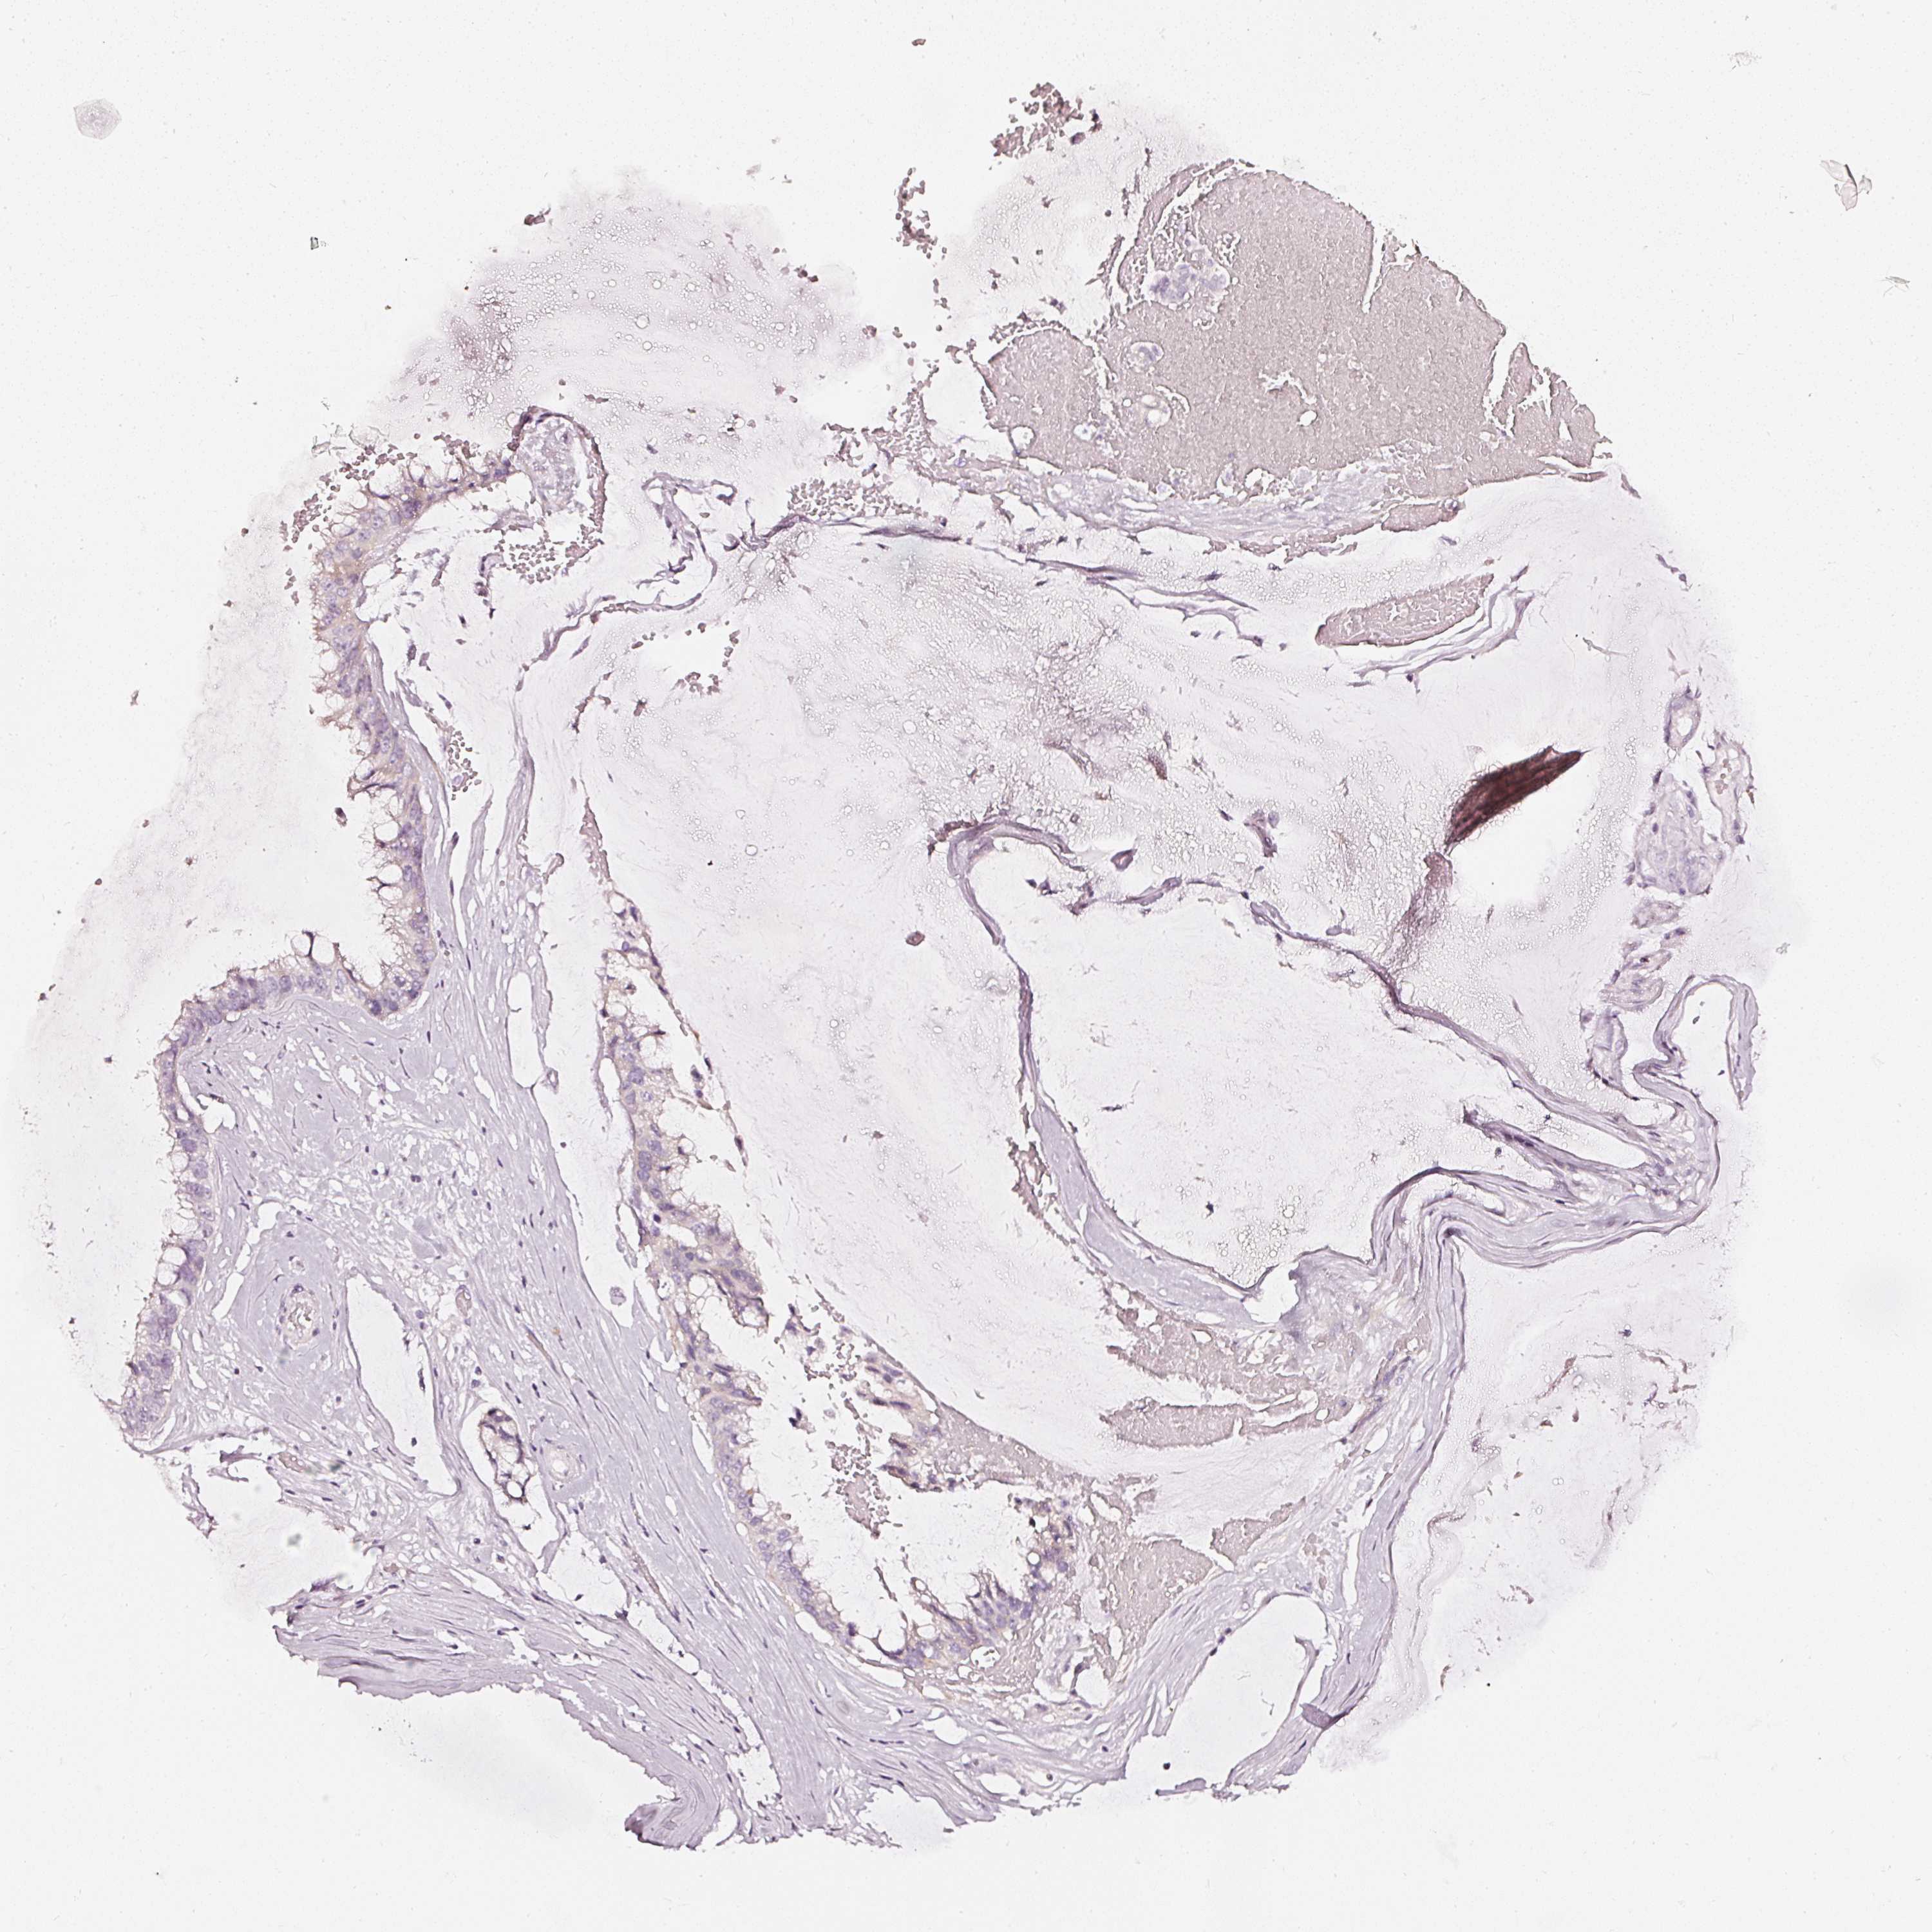

OVARIAN CANCER - Protein expressioni

A mouse-over function shows sample information and annotation data. Click on an image to view it in a full screen mode. Samples can be filtered based on level of antibody staining by selecting one or several of the following categories: high, medium, low and not detected. The assay and annotation is described here.

Note that samples used for immunohistochemistry by the Human Protein Atlas do not correspond to samples in the TCGA dataset.

Antibody stainingi

Antibody staining in the annotated cell types in the current human tissue is reported as not detected, low, medium, or high, based on conventional immunohistochemistry profiling in selected tissues. This score is based on the combination of the staining intensity and fraction of stained cells.

Each image is clickable and will lead to virtual microscopy that enables deeper exploration of all samples and also displays staining intensity scores, fraction scores and subcellular localization as well as patient and tissue information for each sample.

Cystadenocarcinoma, serous, NOS

Carcinoma, endometroid

Cystadenocarcinoma, mucinous, NOS

Carcinoma, NOS